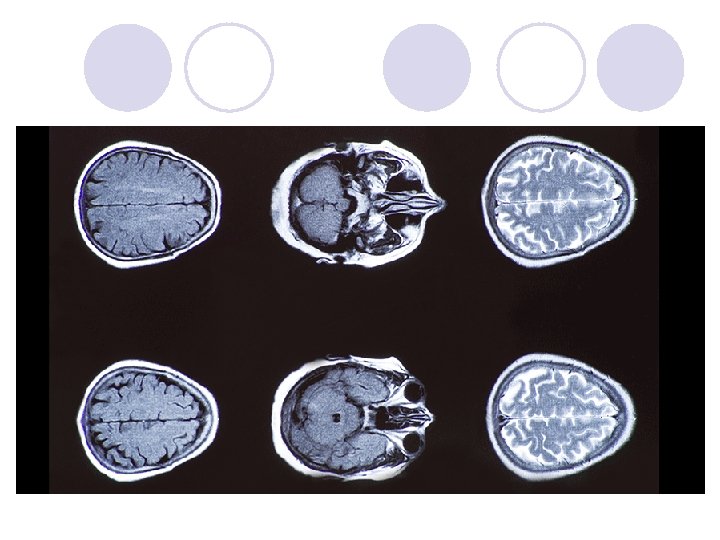

Discuss the Use of Brain Imaging Technologies in Investigating / Biological Factors and Behavior l Magnetic resonance imaging (MRI) ¡ MRI’s are often compared to CT scans because they have the same purpose: to produce a high-resolution three-dimensional image of the brain structure. l Unlike CT scans, MRI’s do not involve X-rays ¡ MRI’s are based on a principle that some atomic nuclei – in particular those of hydrogen atoms – can emit energy when placed in an external magnetic field. l When these pulses of energy are detected by the scanner, the relative distribution of hydrogen atoms in the brain can be mapped. l Hydrogen atoms exist naturally in the body, but their concentration in different types of tissue is different ¡ Advantages: l It allows non-exposure to radiation and, as a consequence, less risk of radiation-induced cancer l MRI has better resolution than a CAT scan. This makes it particularly useful for detecting abnormalities in soft tissue – such as the brain ¡ Disadvantages: l People with metal in their body cannot undergo the procedure (ex. cardiac pacemakers) because metal will attract to the magnetic field • Several deaths have been reported in patients with undisclosed metallic implants l Can be an issue for claustrophobic people because it requires being placed in a narrow tube for a long period of time (~ 45 min) l Lying still can be an issue for young children l Cost: MRI’s are more expensive than CAT scans l High resolution may lead to incidental findings. This may create anxiety and cause patients to seek unnecessary treatment